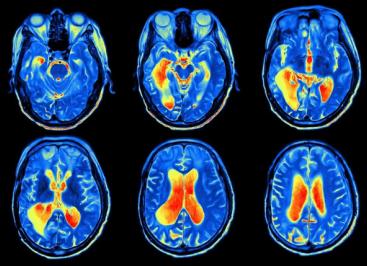

Если вы родились после аварии на ЧАЭС, это не значит, что Чернобыль вас не касается. Острой лучевой болезни у людей, появившихся на свет позже 1986 года, уже не будет. Но риск долгосрочных последствий – от накопленных повреждений клеток до онкологии – никуда не исчез.